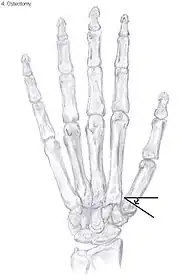

Metacarpal osteotomy

The aim of metacarpal osteotomy is to change the pressure distribution on the TMC joint. The hope is that this will slow the pace of development of osteoarthritis. There is no evidence that this procedure can modify the natural course of TMC OA. Osteotomy may be considered for people with mild arthritis.[24]

During osteotomy, the metacarpal is cut and a wedge shape bone fragment is removed to move the bone away from the hand.[35] Postoperative, the thumb of the patient is immobilized using a thumb-cast.

Possible complications are non-union of the bone, persistent pain related to unrecognized CMC or pantrapezial disease and radial sensory nerve injury.[24]